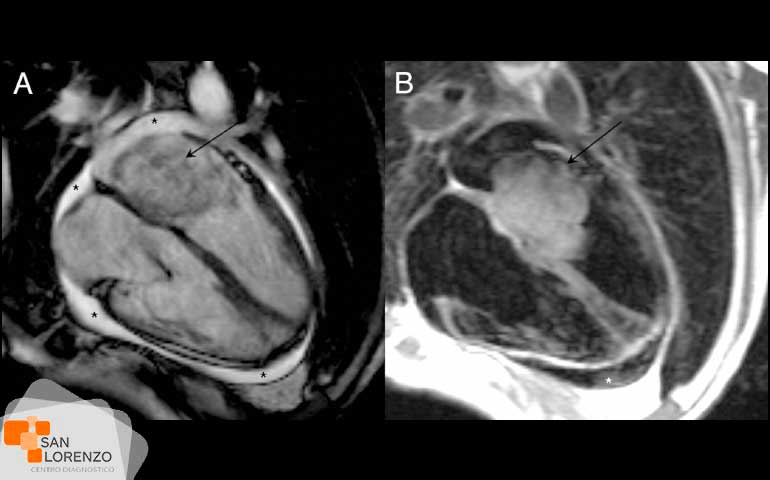

La resonancia magnética cardíaca (RMC) es una técnica de imagen para el estudio del corazón que utiliza ondas de radio potentes para crear imágenes de la estructura interna y alrededor del corazón a través de imágenes de alta resolución, y en centro de diagnóstico San Lorenzo, hacemos posible que en un solo examen podamos obtener información sobre la función y estructuras detalladas del corazón donde están incluidas las cavidades y las válvulas. Gracias a este tipo de examen hoy disponible en Rancagua y región de O’Higgins, podemos obtener imágenes en cualquier plano con alta calidad o definición de imagen, sin la necesidad de viajar a Santiago y con la posibilidad de realizarlo este procedimiento sin ningún tipo de contraste intravenoso.

La resonancia magnética cardíaca, se utiliza para que médicos tratantes puedan determinar la función de cardiopatías congénitas, anomalías de las coronarias, estudios del músculo cardiaco, estudios de función ventricular, estudios de las enfermedades del músculo cardiaco, de la capa de tejido que recubre corazón y masas cardiacas por mencionar algunos.

La resonancia magnética cardíaca se utiliza para determinar la función de cardiopatías congénitas, las anomalías de las coronarias, estudios del músculo cardiaco, estudios de función ventricular, estudios de las enfermedades del músculo cardiaco, de la capa de tejido que recubre corazón y masas cardíacas.